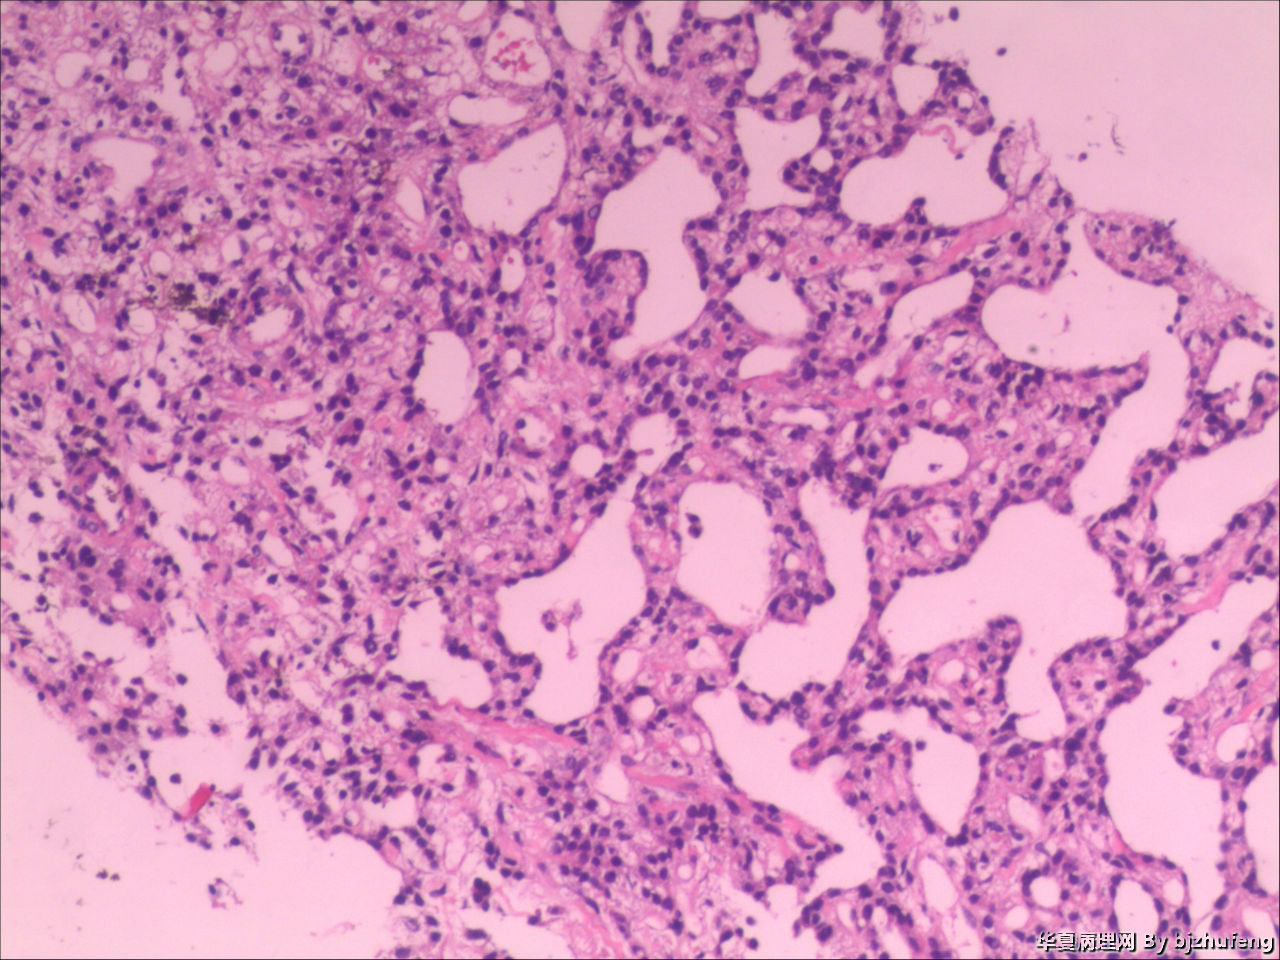

现在还有一种肝癌确诊的“金标准”,那就是做肝脏穿刺。肝脏穿刺的全称是肝脏穿刺活组织检查,就是利用穿刺器材,从患者体内取出2cm的肝脏组织,进行体外培养,观察细胞的病理状况。这种手段准确率高,还不会带来严重的不良反应。只是在进行肝脏穿刺前,我们还要做胸透检查、血常规项目和凝血功能测试。

值得注意的是,肝脏穿刺的临床意义也不止判断肝癌这么简单,它还有许多重要的临床价值。新冠疫情的肝炎就是依赖肝脏穿刺确定合适的药物治疗,我们可以观察肝脏炎症活动,选择易代谢毒性小的药物,还可以利用肝脏穿刺确定肝炎病毒的真身,因为肝炎病毒寄生在肝细胞中,简单的化学抽血检测根本看不出病原体是什么。